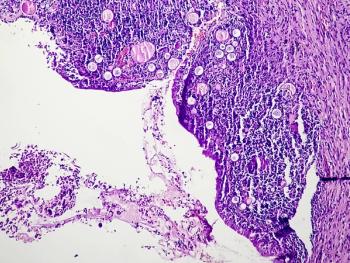

A case report of infiltrative endometriosis without endometrioma underscores the need to consider endometriosis in the differential for patients with pelvic masses and to recognize possible features that might indicate the diagnosis.

Due to the rarity of the disease and its variability in clinical presentation, the condition is hardly recognized by some health care professionals, leading to a delayed diagnosis.